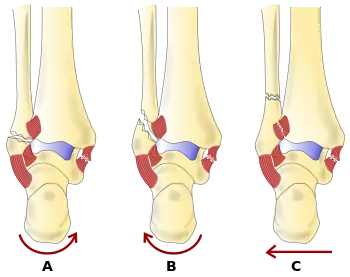

The Danis–Weber classification (often known just as the Weber classification) is a method of describing ankle fractures. It has three categories:[1]

- Type A

Fracture of the fibula distal to the syndesmosis (the connection between the distal ends of the tibia and fibula). Typical features:

- Type B

Fracture of the fibula at the level of the syndesmosis. Typical features:

- Type C

Fracture of the fibula proximal to the syndesmosis. Typical features: